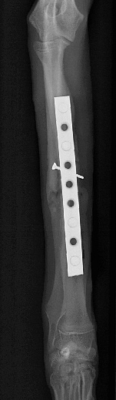

左前肢

左前肢は中和プレートのみなので2期癒合を目指します。

*術後早期は外固定を併用します。

同じく術後19日目 左前肢

左前肢は2期癒合を目指すので、術後2,3週間前後のレントゲンでは

周囲に仮骨形成を認め、また、

骨折部の骨が溶けているように見えます。

これは骨再構築(骨芽細胞、破骨細胞、両方の活動によるもの)

されて起こる現象なので問題ありません。

インプラントの折損、明らかな動揺は認めません。